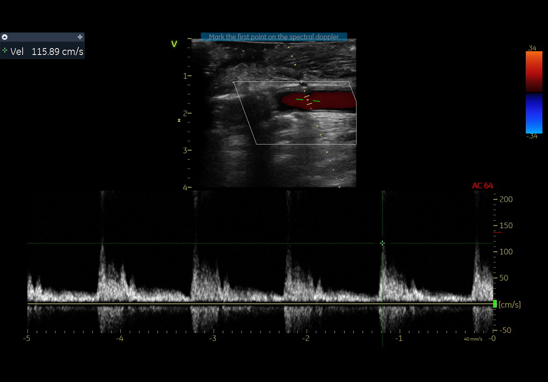

通过右肱动脉置入球囊,术中制造临时性Ⅰ型内漏,实现头臂干血流70%、左颈总动脉60%、左锁骨下动脉40%-50%的维持。